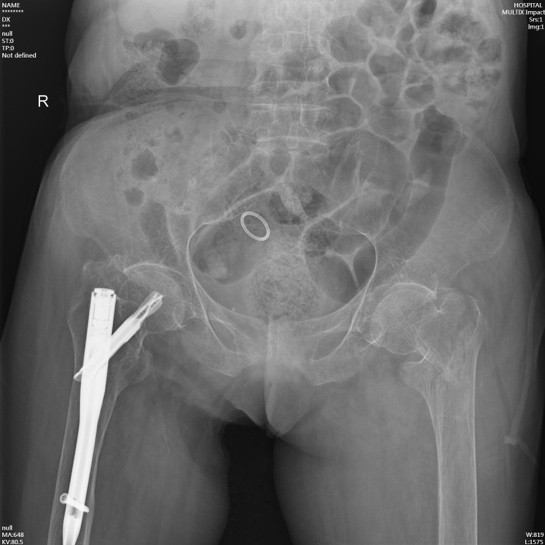

手術(shù)在病人骨折后第三天實(shí)施,手術(shù)當(dāng)天在麻醉科王翔峰主任團(tuán)隊(duì)的緊密協(xié)作,修忠標(biāo)主任醫(yī)師的指導(dǎo)下,鐘水林主治醫(yī)師和韓海醫(yī)師順利地完成了手術(shù),手術(shù)總共耗時30分鐘。

由于患者內(nèi)科基礎(chǔ)疾病較多,為保障其安全,術(shù)后將陳奶奶轉(zhuǎn)移至ICU病房進(jìn)一步治療。在ICU監(jiān)護(hù)期間,陳奶奶出現(xiàn)反復(fù)發(fā)熱、循環(huán)不穩(wěn)等情況,在重癥醫(yī)學(xué)科李紅艷主任醫(yī)師的指導(dǎo)下,制定了相應(yīng)的治療方案。陳奶奶的各項(xiàng)生命體征逐漸穩(wěn)定,后轉(zhuǎn)回我科繼續(xù)治療。